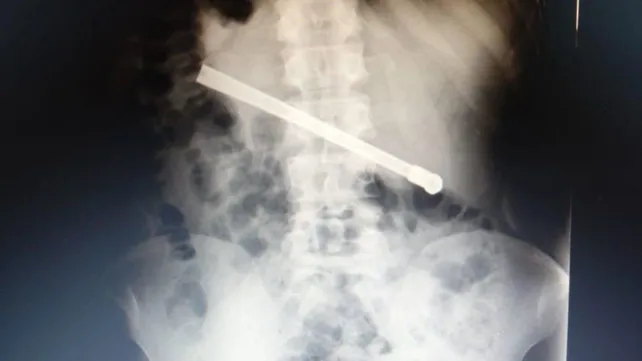

Un preso que se encuentra alojado en el Complejo Penitenciario Rosario (CPR) se tragó una bombilla de mate y tuvo que ser operado en el hospital Eva Perón. El hombre, de 35 años, tenía el objeto atravesado en el tórax y fue intervenido quirúrgicamente este martes.

Al continuar con el malestar, le realizaron una placa radiográfica en la Unidad Penitenciaria ubicada en 27 de Febrero al 7800, y pudieron determinar que había ingerido una bombilla de mate que quedó alojada transversalmente en la cavidad torácica.

En virtud de esto, el interno fue derivado al hospital Eva Perón para recibir una mejor atención, por lo que quedó internado para ser intervenido quirúrgicamente este martes. Tras culminar satisfactoriamente la operación quedará en observación hasta volver al CPR.